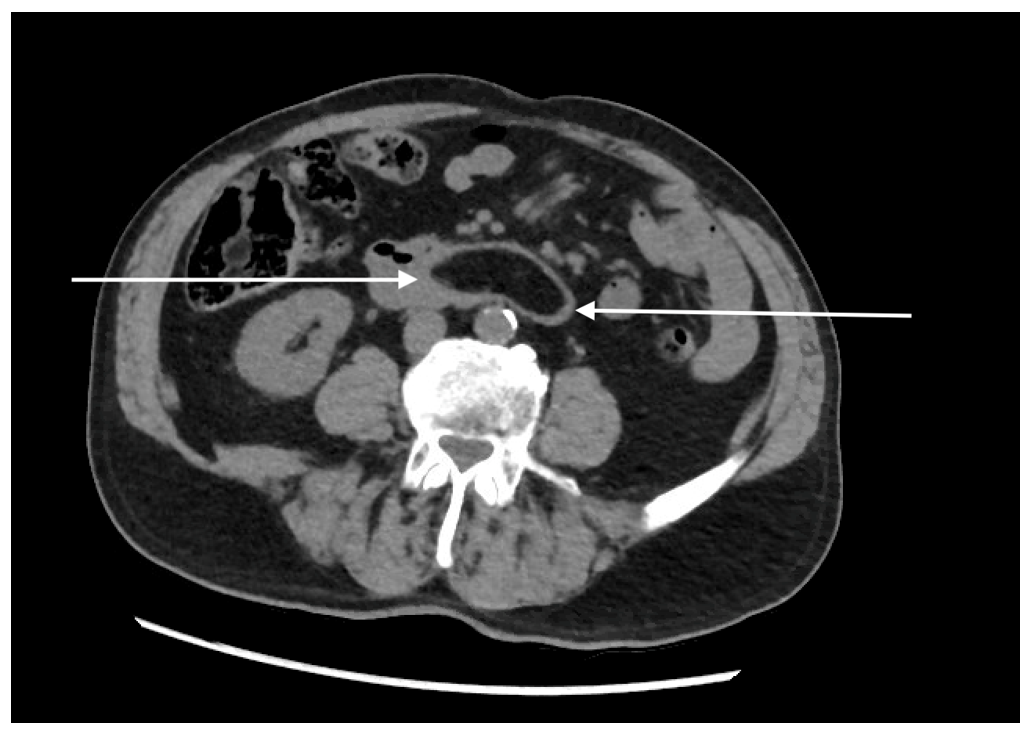

| Figure 2: Computed tomography of the abdomen - transverse section. Duodenal lipoma is indicated with arrows |

Computed tomography (CT) of the abdomen confirmed the presence of a duodenal lipoma extending from the 2nd to 4th part of the duodenum, measuring 95 mm x 30 mm (Figure 1 - 3).

Computed tomography (CT) has grown in popularity for diagnostic purposes in the last decade. Lipomas are easily and reliably identified on CT because of their appearance as a smooth margined mass combined with a characteristic low uniform (fat density) attenuation with a low Hounsfield Unit (HU) count from -70 to -120 HU [28-30].